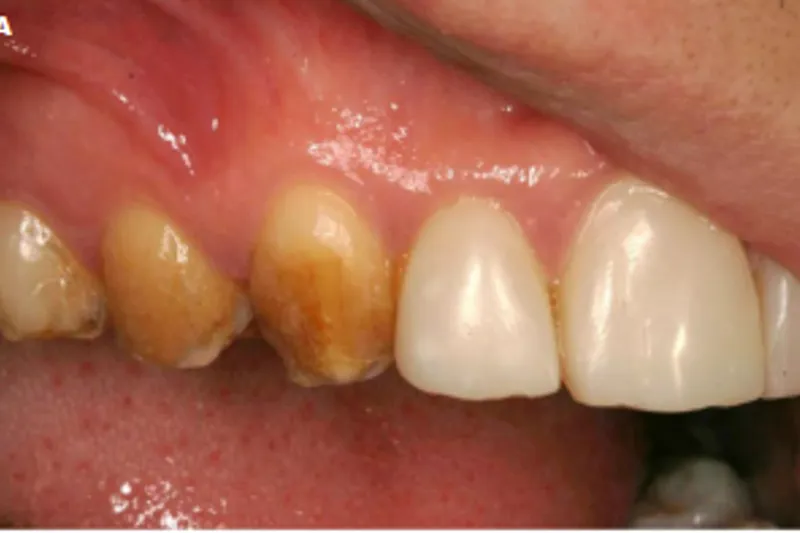

– Patienter med amelogenesis imperfecta har oftest et livslangt behandlingsbehov, fordi insufficient mineraliseret emalje fører til fraktur, slid, symptomer, caries, begrænset holdbarhed af restaureringer og insufficient æstetik. Det er derfor vigtigt, at behandlingsvalg relateres til patientens alder og behov, samt at en noninvasiv tilgang tilstræbes.

– I denne artikel gennemgås behandlingen af en 16-årig dreng med æstetiske problemer i fronten, hvor okklusalt slid endnu ikke er behandlingskrævende. Behandlingsprincippet tager udgangspunkt i patientens unge alder og udføres derfor med direkte plast. De kliniske procedurer bliver udførligt beskrevet undervejs.